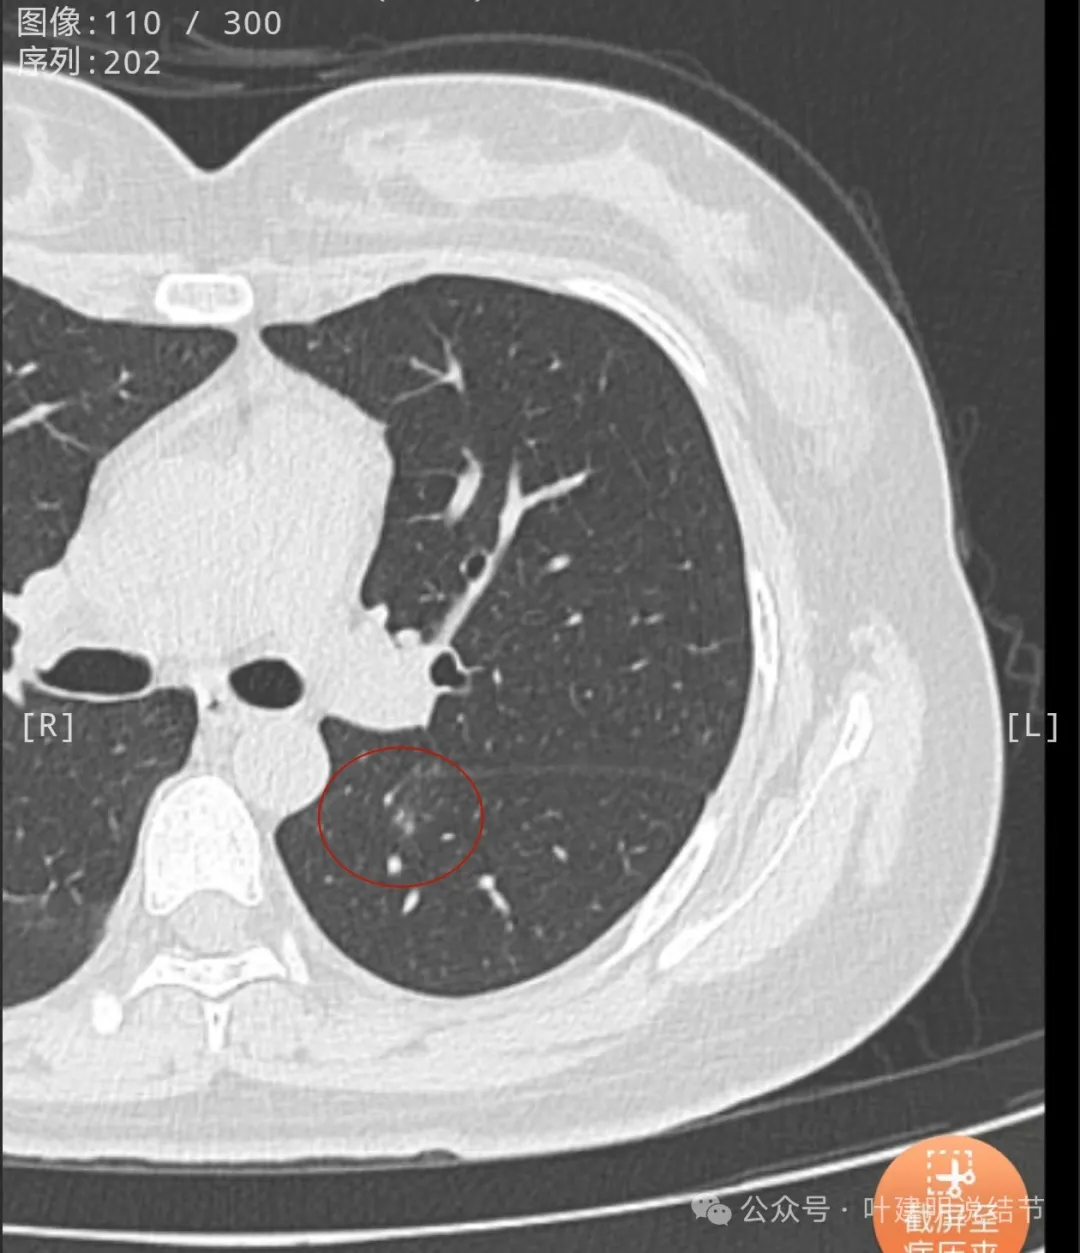

2023年1月首次发现时即是混合密度,大部分是实性的,中间部分密度稍低像磨玻璃,离叶裂较近,整体轮廓较清,表面欠平整。

2023年4月复查没有显著变化,但表面是不平的,密度也是显得杂乱的。

2023年12月再复查,进展倒是并不明显,但边缘似有小棘突状,叶间裂似乎有点牵拉。

2024年10月复查仍无明显进展,表面不平,叶间裂有所牵拉。

病灶现出,密度较高,贴着叶间裂。

叶间裂有牵拉,有微小血管进入病灶,灶内有小空泡征,密度整体显得较高,轮廓清楚,瘤肺边界清。

表面有小棘突或毛刺样征,密度显得杂乱。

轮廓清,小空泡征明显,密度较高,基本上是实性。

边缘区密度较淡。